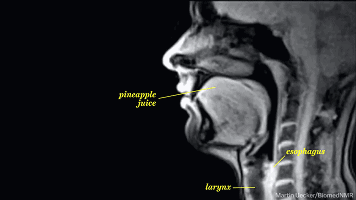

舌头

你以为你的舌头是受你自己支配的?

图样图森破,兴奋使你的舌头开始

躁动,这时候你的舌头已经在嘴里

开始跃跃欲试,要冲破禁锢的牢笼

所以不用我说你也知道要干什么了

随着舌头反映的出现,你的唾液开始

分泌增多,这会使你出现不自主的

吞咽动作。这回你知道自己为什么见到

美女就不停的咽口水了吧,自己想什么

心里没点数么

从下图可以看出两个人的舌头

都开始不老实了,接吻会加剧兴奋

会使心跳速度进一步增加

呼吸也会更急促,全身的肌肉

开始出现不规则的收缩肌紧张